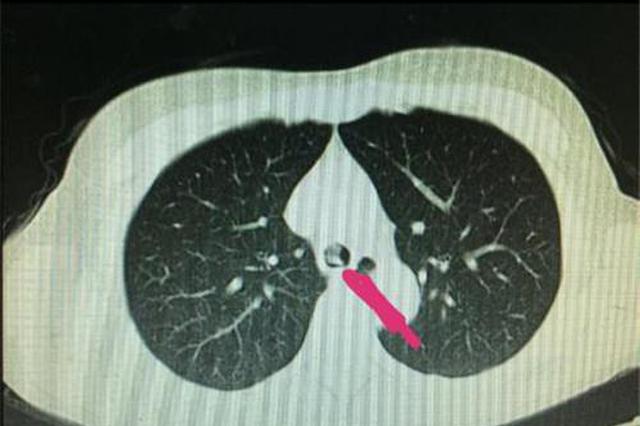

天下之大无奇不有,常州一中年女子喝了口水不巧假牙掉了,结果一个不小心,把假牙喝进了气管!这个假牙还挺大,一呛进气管,就剧烈咳嗽,根本咳不出来不说,女子还无法说话了!最终,常州市第三人民医院的医生通过微创手术帮助其取出。

一瞬间,刘女士咳嗽不止,不能讲话。她也采取了很多办法,想把假牙咳出来,可是她发现似乎并不可能。意识到这很危险,刘女士很快赶到了三院接受治疗。医生为其拍了片,发现假牙就卡在一侧肺里,堵住了气道。这颗假牙比较大,加上又是高分子塑料材质的,取出来难度较大。在通过一系列术前研判后,三院医生决定决定为其实施硬质气管镜手术取出假牙。